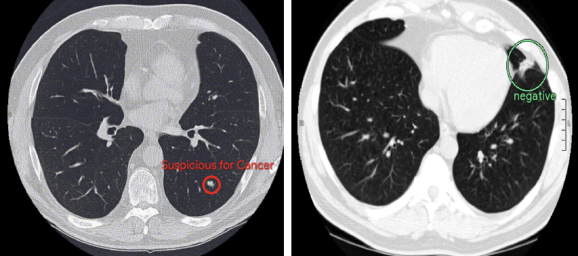

폐암은 암 중에서도 가장 사망 비율이 높은 질병이다. 구글은 이런 폐암을 검출하기 위한 AI를 개발 중이다. AI가 LDCT를 이용한 암 ...